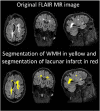

Different neurodegenerative diseases can cause memory disorders and other cognitive impairments. The early detection and the stratification of patients according to the underlying disease are essential for an efficient approach to this healthcare challenge. This emphasizes the importance of differential diagnostics. Most studies compare patients and controls, or Alzheimer's disease with one other type of dementia. Such a bilateral comparison does not resemble clinical practice, where a clinician is faced with a number of different possible types of dementia. Here we studied which features in structural magnetic resonance imaging (MRI) scans could best distinguish four types of dementia, Alzheimer's disease, frontotemporal dementia, vascular dementia, and dementia with Lewy bodies, and control subjects. We extracted an extensive set of features quantifying volumetric and morphometric characteristics from T1 images, and vascular characteristics from FLAIR images. Classification was performed using a multi-class classifier based on Disease State Index methodology. The classifier provided continuous probability indices for each disease to support clinical decision making. A dataset of 504 individuals was used for evaluation. The cross-validated classification accuracy was 70.6% and balanced accuracy was 69.1% for the five disease groups using only automatically determined MRI features. Vascular dementia patients could be detected with high sensitivity (96%) using features from FLAIR images. Controls (sensitivity 82%) and Alzheimer's disease patients (sensitivity 74%) could be accurately classified using T1-based features, whereas the most difficult group was the dementia with Lewy bodies (sensitivity 32%). These results were notable better than the classification accuracies obtained with visual MRI ratings (accuracy 44.6%, balanced accuracy 51.6%). Different quantification methods provided complementary information, and consequently, the best results were obtained by utilizing several quantification methods. The results prove that automatic quantification methods and computerized decision support methods are feasible for clinical practice and provide comprehensive information that may help clinicians in the diagnosis making.